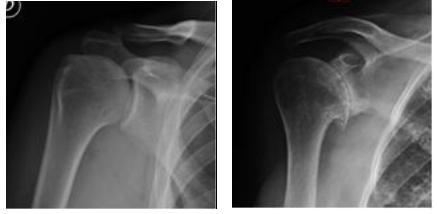

La più frequente è l’artrosi, che comporta rispetto alla spalla normale (fig. 3) la perdita delle cartilagini di rivestimento con conseguente scomparsa dello spazio articolare tra omero e scapola, la deformazione delle superfici articolari e la formazione di escrescenze ossee dette osteofiti (fig. 4): a volte avviene spontaneamente con l'invecchiamento, altre volte è favorita e condizionata da danni precedenti all’articolazione, ad esempio traumi severi o le ripetute lussazioni di spalla.